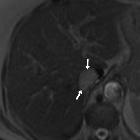

Isolated

intracaval recurrence of resected renal carcinoma. Unenhanced T2- (a-d) and T1-weighted (e) images showed tumour thrombosis in the intrahepatic vena cava (arrows) and normal flow-void signal at the hepatic vein confluence (arrowheads).